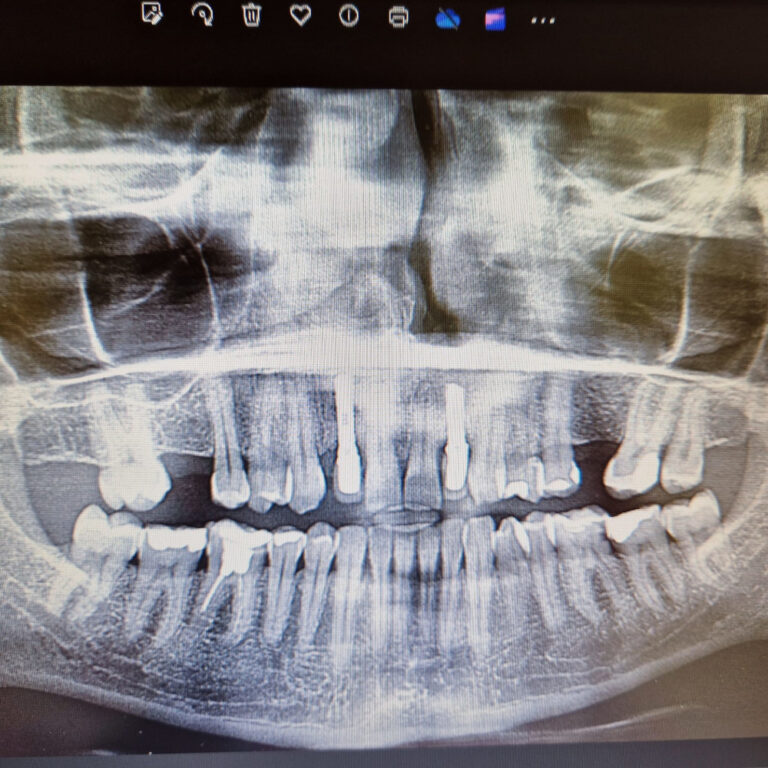

Ortodoncja CBCT

Leczenie chirurgiczno-ortodontyczne wad zębowych z zastosowaniem tomografii spiralnej CBCT w naszej klinice.